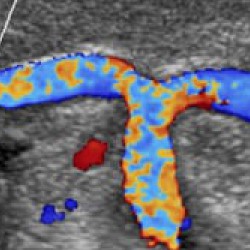

• Функция Auto Doppler автоматизирует рутинные действия, связанные с исследованием сосудов. Она улучшает шкалу серого, автоматические параметры допплеровского режима, корректирует углы и цвет.

Трехмерная реконструкция ЦДК:

Да

Цветовой допплер:

• Цветной допплер (CD) - Да

• Опция получения трехмерного изображения в режиме цветового допплеровского картирования (трехмерная реконструкция ЦДК) - Да

• Опция получения трехмерного изображения в режиме цветового допплеровского картирования - Да